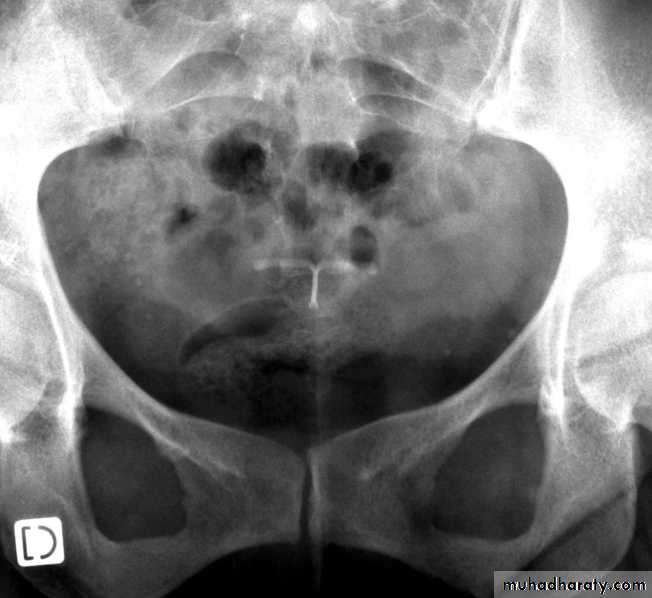

Ultrasound imaging

Copper IUDLNG IUD